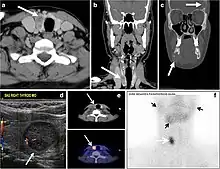

Fig. 8. A 48-year-old male patient post total thyroidectomy with PTC recurrence. a Transverse greyscale ultrasound of the neck demonstrates a left thyroid bed heterogeneous, predominantly hypoechoic irregular lesion with calcifications (white arrow). b A spot image of iodine 123 total body scan of the neck demonstrate a focus of abnormal radiotracer uptake at the left thyroid bed (Black arrows) between the annotated markers. c Enhanced axial CT scan of the neck demonstrates an enhancing large left thyroid bed mass (white arrow) with no calcifications. The lesion exerts a mass effect on the oesophagus (black arrow) and is inseparable from the trachea.[1]

Fig. 9. A 58-year-old male patient with persistence PTC at thyroid bed with hypervascular nodal metastasis. a–c Transverse greyscale and colour Doppler neck ultrasound demonstrate hypoehoic soft tissue in the left thyroid bed (white arrow in a). There are a heterogeneous enlarged lymph nodes at level 2 and 3 with markedly increased vascularity (white arrow in b and c). d–f Enhanced axial CT images of the neck demonstrate a 2.7 × 1.4 cm hypodense soft tissue lesion anterior to the left carotid sheath (white arrow). There are left-sided enhancing abnormal and enlarged lymph nodes at cervical level 2 and 3 (black arrows).[1]